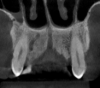

Figure 3. Coronal view of the anterior maxilla presenting the “s-shaped” canalis sinuosus on the right side.

Figure 3

Knowledge of anatomical variations is extremely important for planning treatment and avoiding complications postoperatively. Precise imaging becomes especially important in surgical cases that might involve vulnerable structures, including sinus cavities, nerve channels, or blood vessels. One of the variations rarely discussed is the canalis sinuosus, a neurovascular canal, nerve branch of the infraorbital canal, that passes the anterior superior alveolar nerve (Figure 3).4